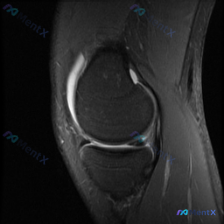

主诉半月板异常?单张膝关节MRI的分析思路整理

本次仅提供放射影像-膝盖MRI-T2序列-矢状位单张图像,用户核心关切为「半月板异常」。

影像基础评估结果

我们先逐层看解剖结构:

- 骨骼结构:股骨远端及胫骨近端骨髓信号无明显弥漫性高信号,无急性骨挫伤表现;骨皮质轮廓清晰,无明显骨折线或骨赘

- 关节软骨:股骨髁关节软骨表面连续,无局灶性缺失或深层信号异常

- 半月板:可见的前角及体部为正常低信号,形态规整,没有明确的内部高信号裂隙延伸到关节面

- 交叉韧带:前后交叉韧带走行自然,连续性好,信号均匀无增高、水肿

- 关键阳性发现:髌上囊区域和髌股关节间隙可见明显条带状T2高信号,提示中大量膝关节积液,以髌上囊区域为主